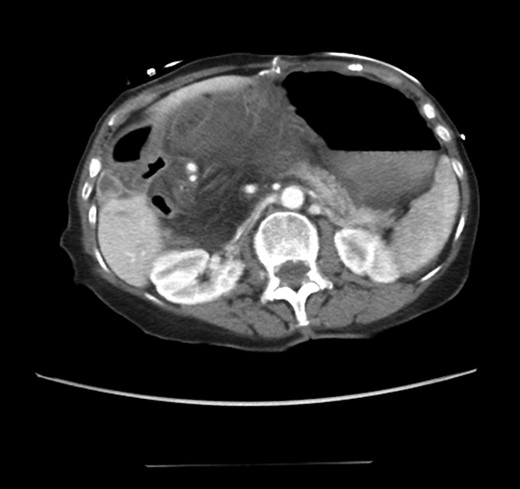

An 81-year-old female with a medical history of CAD with stents, hyperlipidemia, hypothyroidism, GERD, recent UTI, pancreatic cyst, constipation, anemia and leukopenia presented to the ED with a 1 day history of mild, diffuse and cramping abdominal pain. The patient was unable to give an accurate history, but the son at bedside supplemented this reporting that for several years the patient had been experiencing ill-defined abdominal discomfort. Physical exam showed a soft abdomen with mild tenderness and no evidence of peritonitis. A CT scan of the abdomen and pelvis with IV and PO contrast (Fig. 1) showed edematous changes to the mesentery of the small and large bowel with swirling of vessels indicative of internal hernia. The stomach was also noted to be distended with both air and fluid as a consequence of posterior compression by the hernia contents (Fig. 2). A surgical consult was obtained, a nasogastric tube and Foley catheter were placed, antibiotics were started, and the patient was taken for an exploratory laparotomy. Upon entering the abdomen through a vertical midline incision, 1.5 l of ascites was drained revealing a diffusely edematous mesentery. A large portion of the small bowel was seen to be herniated through the Foramen of Winslow (Fig. 3). A Kocher maneuver and division of the gastrocolic ligament were then performed to allow release of the herniated small bowel. It was at this time that, in addition to small bowel, a large portion of the ascending and transverse colon was noted to be herniated through the foramen of Winslow. The small bowel was also seen to be torsed about its own mesentery. Normal anatomy was restored and the bowel noted to be healthy and viable with peristalsis (Fig. 4). Due to the large size of the foramen after reduction and enlargement, it was deemed best to leave it open to prevent any further incarceration or strangulation. The abdomen was closed and the patient tolerated the procedure well. At a follow-up visit 2 months later, the patient had well-healed incisions, was doing well, tolerating a diet, and gaining weight appropriately.

Diagnosing an internal hernia is frequently accomplished using physical exam and CT imaging. Abdominal X-ray does have some nonspecific findings suggestive of internal hernia but is usually inadequate for diagnosis. Diagnosis of a foramen of Winslow hernia, however, is only accomplished in 10% of patients preoperatively [3]. As previously mentioned this diagnosis is rare and often presents with vague obstructive type symptoms. This likely contributes to the low occurrence of accurate preoperative diagnosis. However, several radiographic findings were seen in this patient that suggested a foramen of Winslow hernia preoperatively. First, there is visible swirling of the mesentery on the CT scan that is indicative of internal hernia (Fig. 1). Second, there are loops of small bowel that can be visualized between the IVC and the edge of the liver in a supra renal position along the lesser curvature of the stomach (Figs 1 and 2). When compared to a CT of the abdomen and pelvis obtained 4 years prior to presentation, there is actually evidence that this patient had a non-obstructing foramen of Winslow hernia at that time as demonstrated by bowel being visualized in the lesser sack (Fig. 5). These findings, especially small bowel along the lesser curvature of the stomach, are inconsistent with normal anatomy and strongly indicative a foramen of Winslow hernia.

CT abdomen and pelvis coronal view of foramen of Winslow hernia.